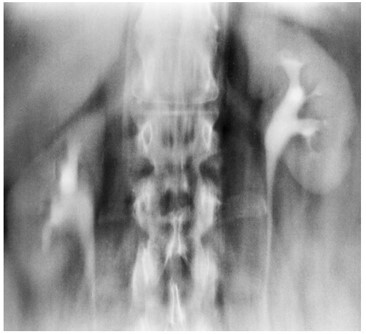

3

Q

What pathology is seen here?

A

Unilateral Renal Agenesis

How well did you know this?